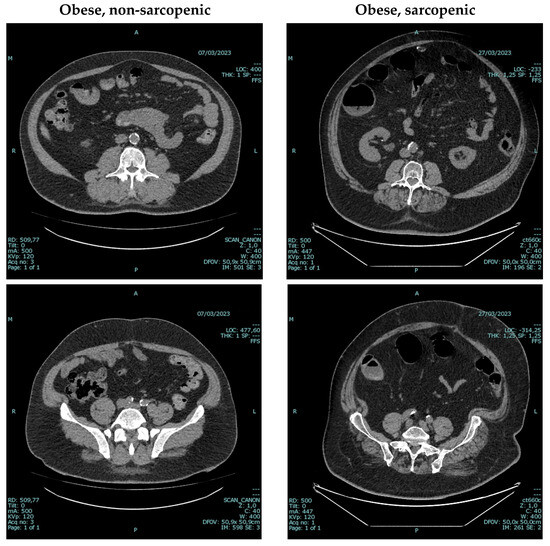

- Bellizzi, V.; Annunziata, G.; Albanese, A.; D’Alessandro, C.; Garofalo, C.; Foletto, M.; Barrea, L.; Cupisti, A.; Zoccali, C.; De Nicola, L. Approaches to patients with obesity and CKD: Focus on nutrition and surgery. Clin. Kidney J. 2024, 17, 51–64. [Google Scholar] [CrossRef]

- Tolonen, A.; Pakarinen, T.; Sassi, A.; Kytta, J.; Cancino, W.; Rinta-Kiikka, I.; Pertuz, S.; Arponen, O. Methodology, clinical applications, and future directions of body composition analysis using computed tomography (CT) images: A review. Eur. J. Radiol. 2021, 145, 109943. [Google Scholar] [CrossRef]

- Donini, L.M.; Busetto, L.; Bischoff, S.C.; Cederholm, T.; Ballesteros-Pomar, M.D.; Batsis, J.A.; Bauer, J.M.; Boirie, Y.; Cruz-Jentoft, A.J.; Dicker, D.; et al. Definition and Diagnostic Criteria for Sarcopenic Obesity: ESPEN and EASO Consensus Statement. Obes. Facts 2022, 15, 321–335. [Google Scholar] [CrossRef]

- Chianca, V.; Albano, D.; Messina, C.; Gitto, S.; Ruffo, G.; Guarino, S.; Del Grande, F.; Sconfienza, L.M. Sarcopenia: Imaging assessment and clinical application. Abdom. Radiol. 2022, 47, 3205–3216. [Google Scholar] [CrossRef] [PubMed]

- Sabatino, A.; Regolisti, G.; Benigno, G.; Di Mario, F.; Avesani, C.M.; Fiaccadori, E. Low skeletal muscle mass by computerized tomography is associated with increased mortality risk in end-stage kidney disease patients on hemodialysis. J. Nephrol. 2022, 35, 545–557. [Google Scholar] [CrossRef] [PubMed]